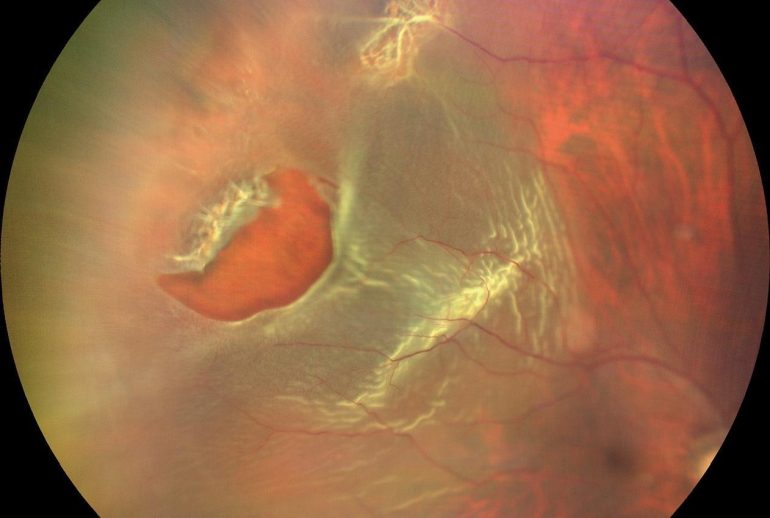

پارگی شبکیه یکی از اختلالات جدی چشم است که در آن، شبکیه که لایه نازک و حساسی در پشت چشم است، از جایگاه اصلی خود جدا میشود. این مشکل میتواند منجر به از دست دادن دید مرکزی یا حتی نابینایی کامل شود، بهویژه اگر درمان به موقع انجام نشود. پارگی شبکیه بیشتر در افرادی رخ میدهد که به دلایل مختلف، بافت شبکیهشان آسیبپذیرتر است. در موارد شدید، این وضعیت میتواند به جداشدگی کامل شبکیه منجر شود که نیاز به جراحی فوری دارد.

علائم پارگی شبکیه

علائم پارگی شبکیه معمولاً به صورت ناگهانی ظاهر میشوند و میتوانند شامل موارد زیر باشند:

دیدن جرقههای نور

یکی از نشانههای اولیه پارگی شبکیه، مشاهده جرقههای نوری است که معمولاً در محیط تاریک یا در حرکت چشم احساس میشود.

دیدن سایه یا پرده در دید

احساس وجود سایهای که بخشی از دید را مسدود میکند، از نشانههای جدی پارگی شبکیه است.

تشخیص پارگی شبکیه

معاینه فوندوسکوپی

این معاینه با استفاده از ابزارهای خاص انجام میشود و به پزشک امکان میدهد تا شبکیه را به طور دقیق بررسی کند.